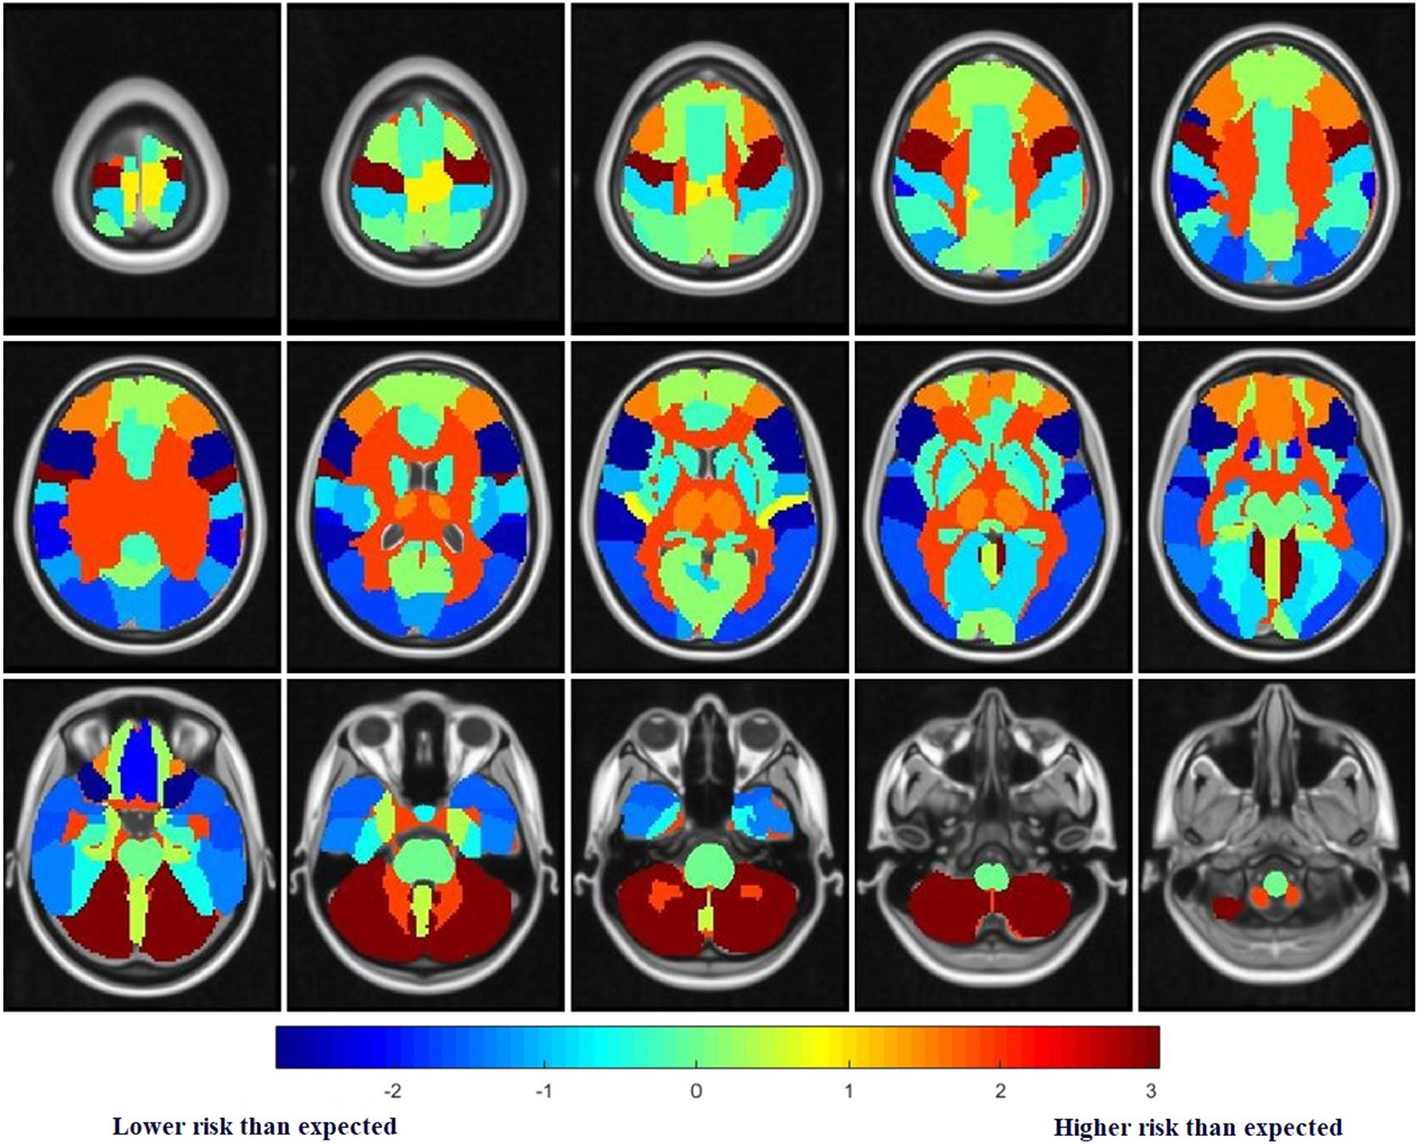

In this study, 215 SCLC patients with brain metastases from three hospitals in China were included. The research team marked a total of 1,026 metastases on the Magnetic Resonance Imaging data and mapped all metastases to the standard brain template with the image registration algorithm, and then the standard brain template was automatically divided into 47 brain regions according to the brain atlas.

On the basis of that processing, the metastasis probability of each brain region was counted, and the difference between the actual metastasis in each brain region and the expected metastasis probability was compared by using a statistical test. Finally, the metastasis risk level of each brain region was determined, and the brain metastasis risk map of SCLC was established.

The risk map showed that the brain regions at a high metastasis risk include the cerebellum, deep white matter and brain stem, and the regions at a low metastasis risk are the temporal lobe and inferior frontal gyrus.

Fig. Brain metastasis risk map of SCLC. The redder the brain region, the higher the metastasis risk; the bluer the region, the lower the metastasis risk.(Image by SIBET)